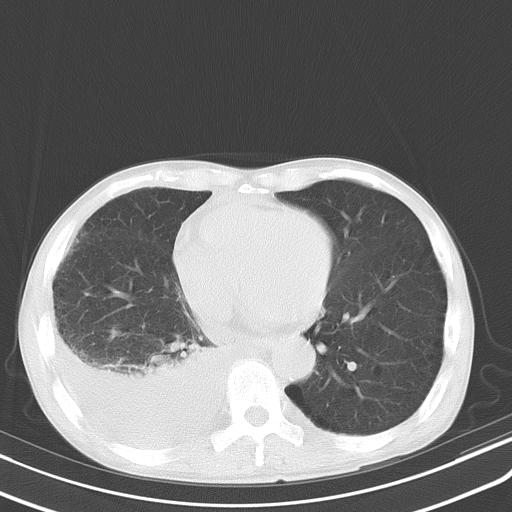

男性 75  咳嗽 一周前发热最高达39

右肺继发型tb并右侧tb性胸腔炎,右侧胸腔大量积液并右下肺膨胀不全,慢支肺气肿、多发肺大泡。建议抽胸水实验室检查并复查排除恶性在占位。

右上肺继发型肺结核,右胸腔中等量积液。

结核的基础上有纵隔淋巴结肿大,右侧有胸水,但右侧纵隔反而窄,说明有肺有不张。

再就是右下肺有块影,和不张混合,还是不能除外肺癌。

补充材料,患者2月份ct片大致正常,双侧胸腔积液,2月份抽胸水未发现ca细胞,现患者发热,痰多,各气管通畅,

1)右肺继发型肺结核。2)左肺胸膜下多发性肺大泡。3)右侧胸腔积液。